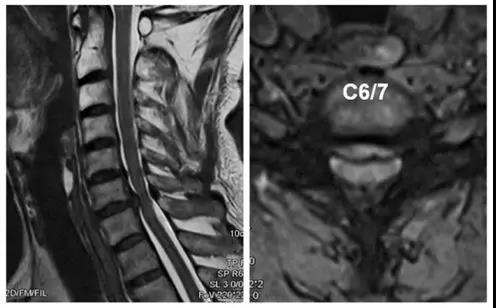

术前X线

术前CT

术前核磁

术后X线正侧位片

患者:男,51岁

主诉:双上肢麻木、疼痛一月,加重伴行走不稳3天

诊断:

1.颈椎间盘突出症(C6/7);

2.混合型颈椎病。